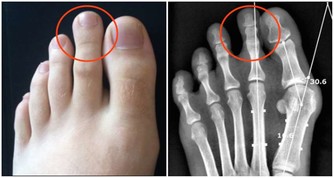

3. 便便變細,排不盡

若是平時排的便便較粗,突然間變成了鉛筆一般的柔軟細便,並且總有排不盡的感覺,就要特別注意有可能是大腸癌導致的,需要高度警惕,必要時到正規醫院消化內科就診。